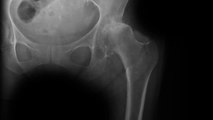

Johnson & Johnson was ordered by a Texas jury to pay more than $1 billion to a group of plaintiffs over artificial hip replacements. Officials of J&J’s DePuy unit, which produces the hip replacements, knew the hip replacements were faulty but failed to warn doctors. The company now faces more than 9,000 lawsuits accusing them of mishandling the metal hips. The verdict includes more than $30 million in actual damages for the six plaintiffs and more than $1 billion in punitive damages, according to court filings. The company stopped selling the devices in 2013 after the U.S. Food and Drug Administration toughened artificial-hip regulations.